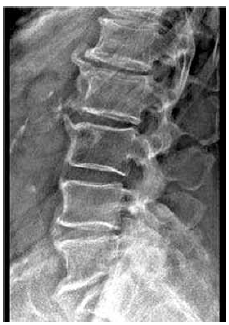

Considere a principal alteração demonstrada na radiografia de coluna a seguir.

A principal hipótese diagnóstica é